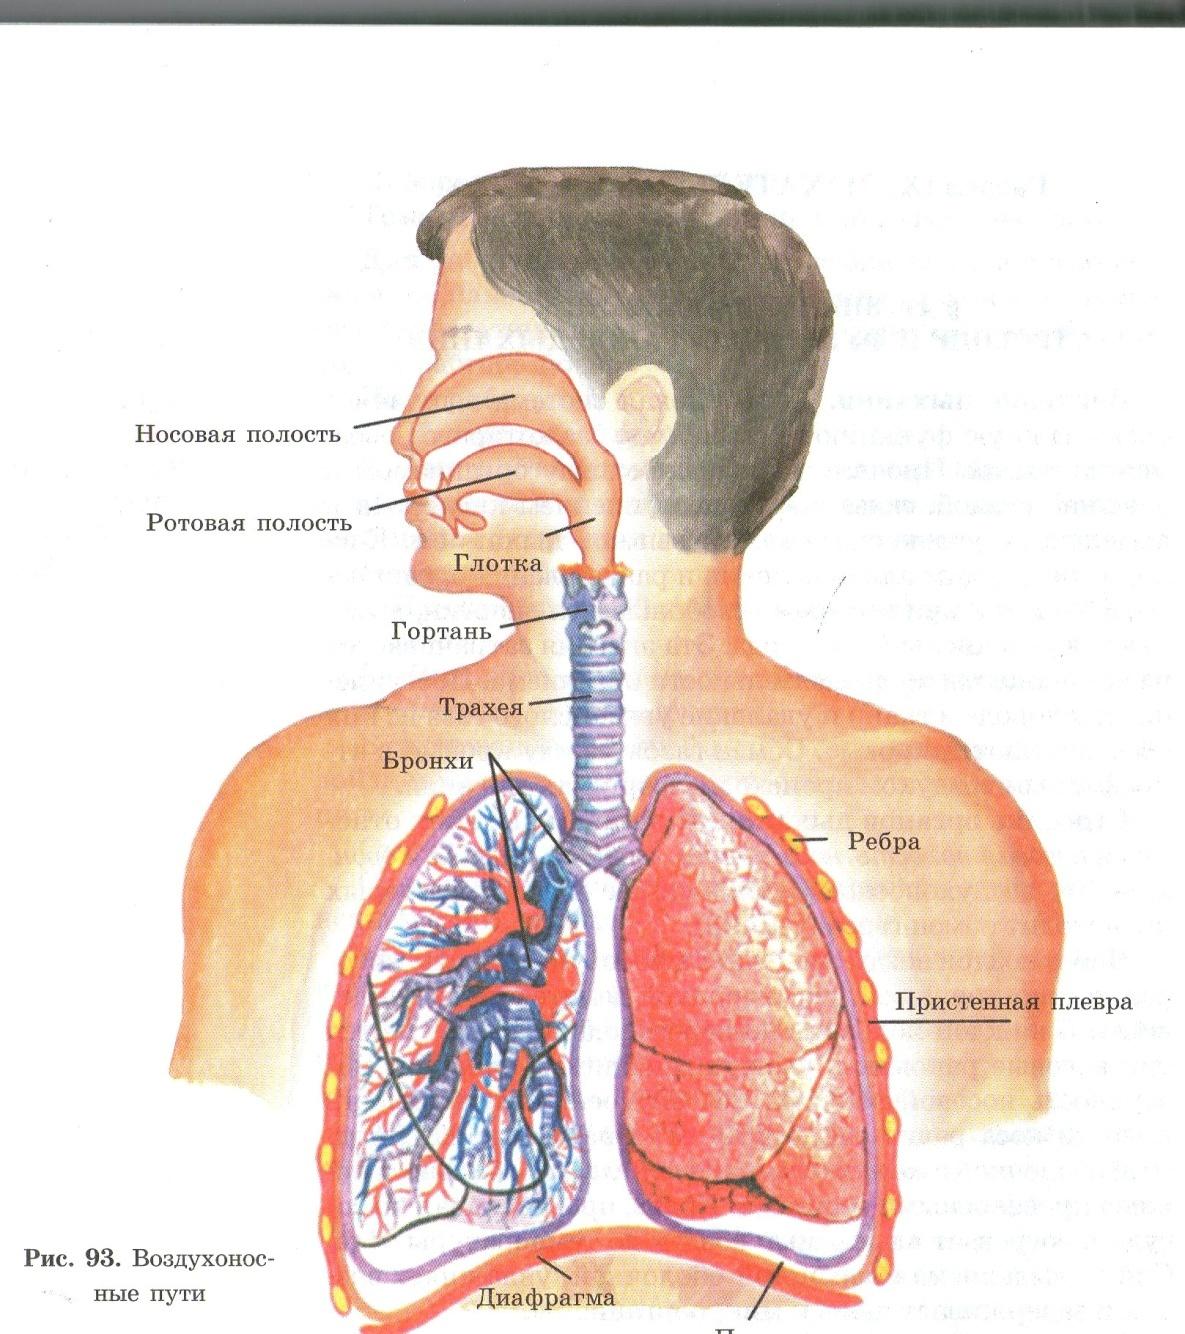

Здоровье дыхательной системы: бронхи и легкие